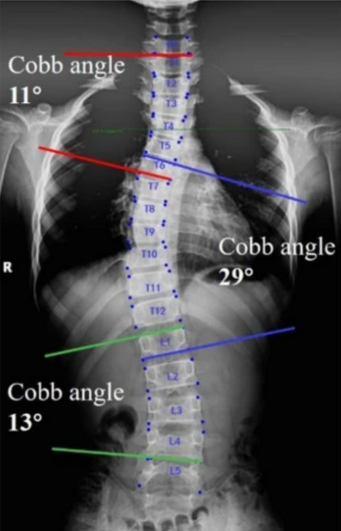

The Cobb Angle is the standard radiographic method for quantifying spinal curvature in scoliosis and assessing the severity of coronal plane deformity.

It measures the angle between the most tilted vertebrae at the upper and lower ends of a spinal curve, providing an objective estimate of curve magnitude.

• Identify the upper end vertebra (most tilted vertebra at the top of the curve) and the lower end vertebra (most tilted at the bottom).

• Draw a line along the superior endplate of the upper end vertebra and another along the inferior endplate of the lower end vertebra.

• Construct perpendicular lines to each of these endplate lines.

• Measure the angle formed at their intersection — this is the Cobb Angle.

• If multiple curves exist (e.g., thoracic and lumbar), repeat the process for each curve.

• Normal spinal alignment: Cobb angle < 10°; no structural scoliosis

• Mild scoliosis: Cobb angle = 10-25°; observation and surveillance imaging indicated

• Moderate scoliosis: Cobb angle = 25-45°; bracing often recommended (especially in skeletally immature patients)

• Severe scoliosis: Cobb angle >45-50°; surgical correction typically indicated

In double or triple curves, each curve’s Cobb angle should be measured and labeled (e.g., T4–T10 = primary thoracic; T11–L3 = lumbar compensatory).